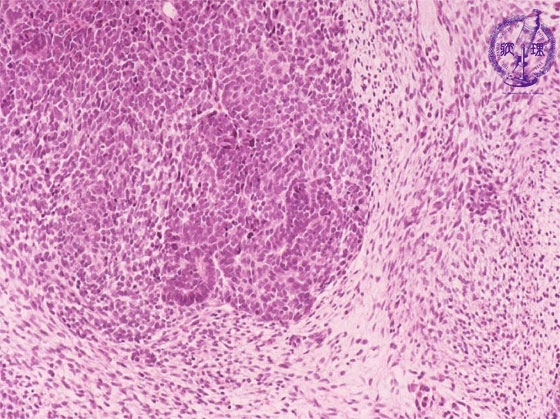

- (16)Nephroblastoma (Wilms tumor)

Microscopic findings ( HE, middle power view): Th tumor is composed of (1) blastemal, (2) organoid and (3) stromal elements (each shown by dotted lines).